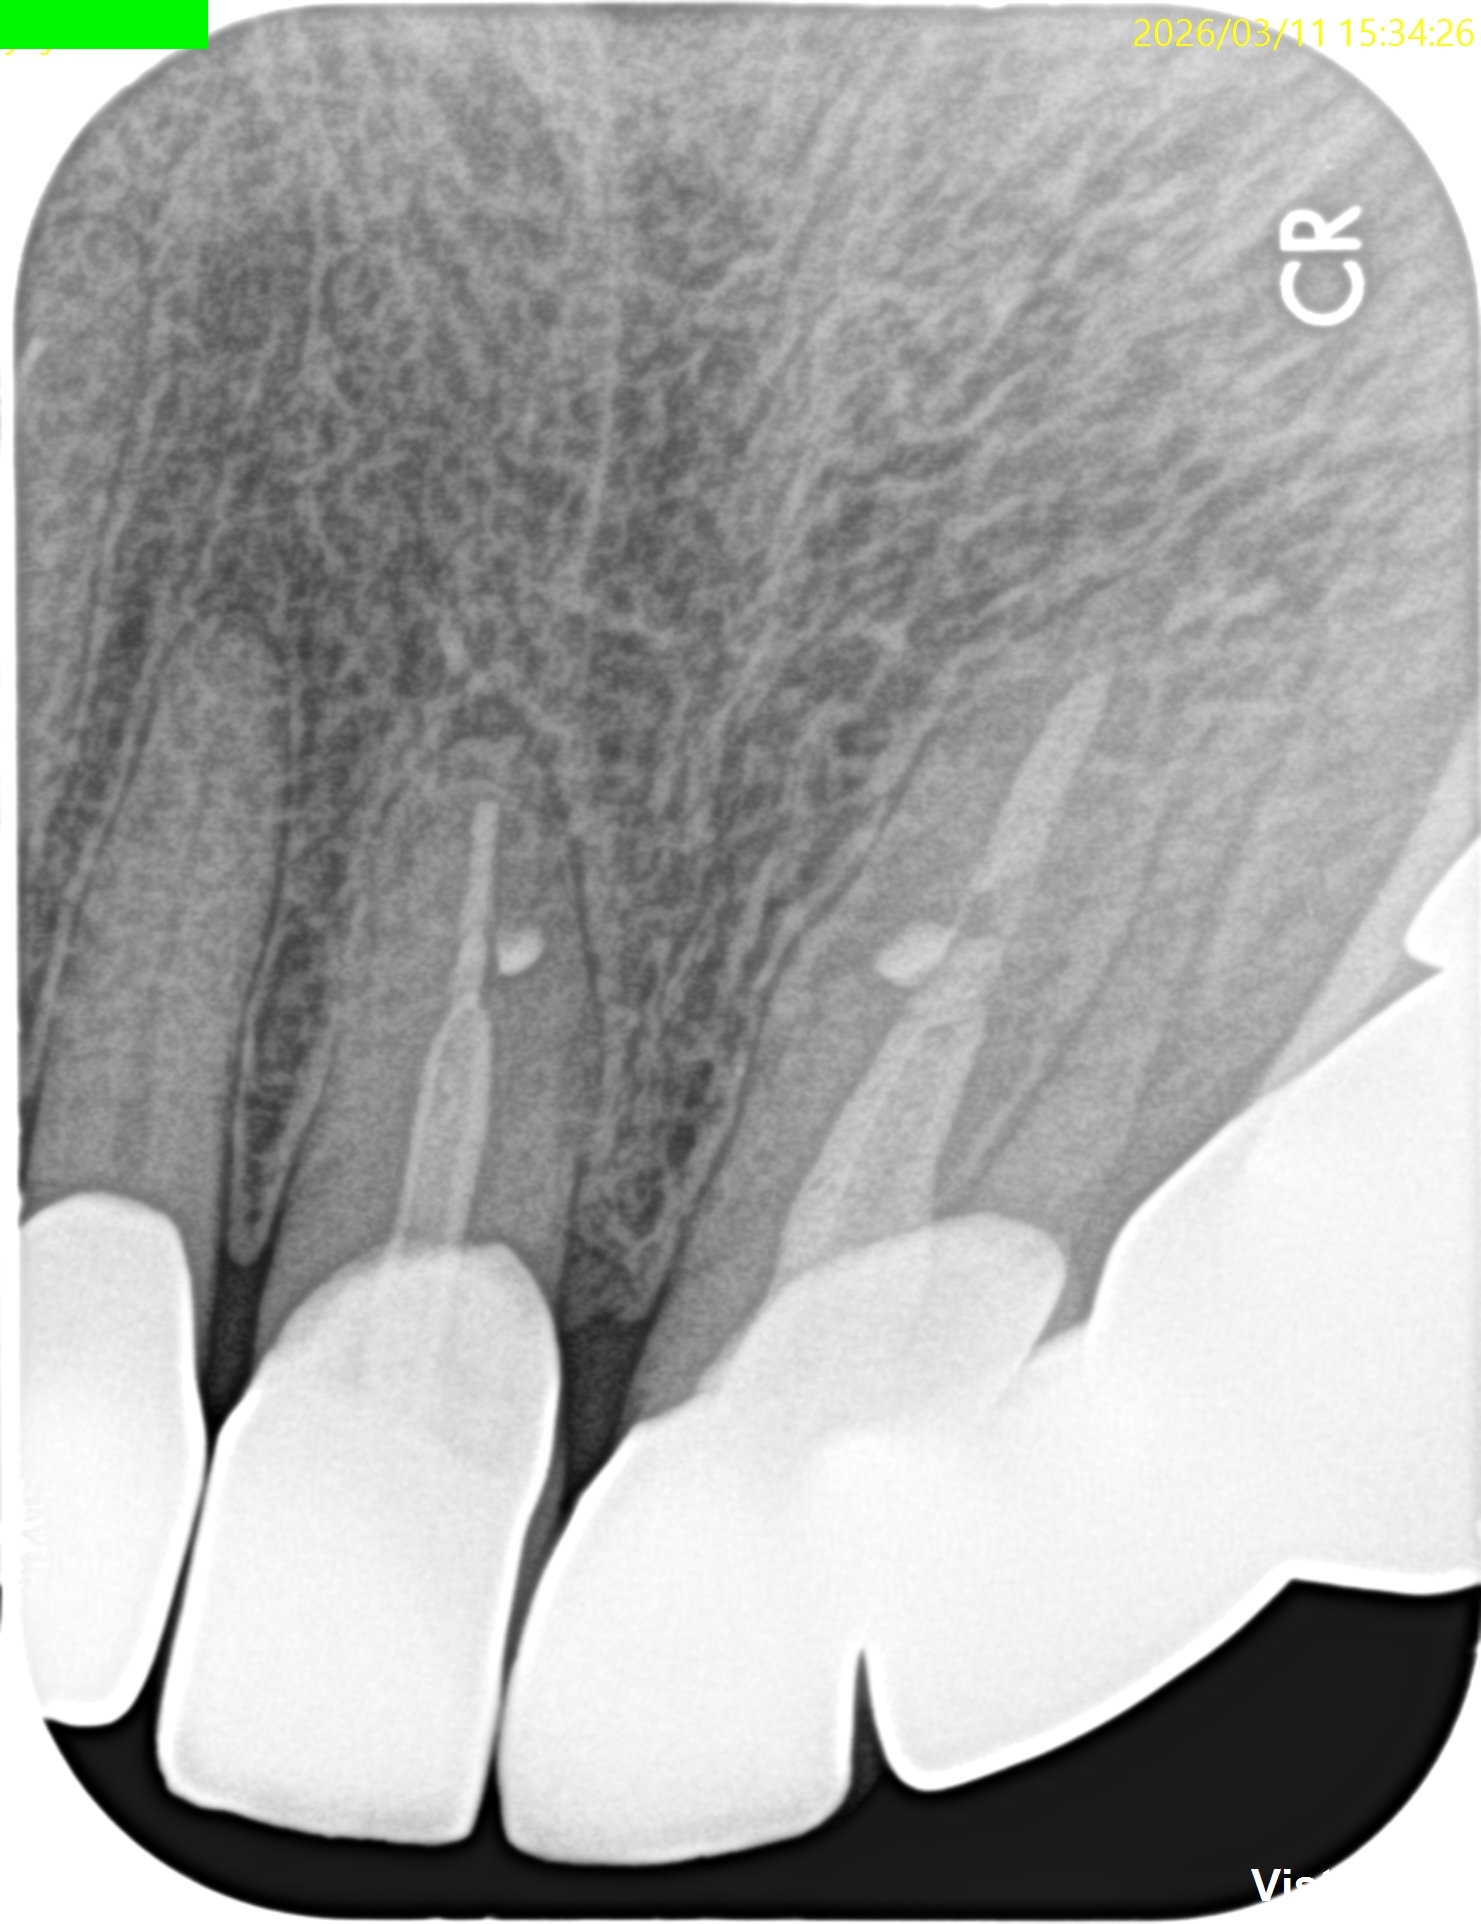

#8,9 Microsurgery 1yr recall(2026.3.11)

#8,9(B)

初診時と比較した。

問題は大きく解決されている。

初診時のSinus tract, 臨床症状は消失した。